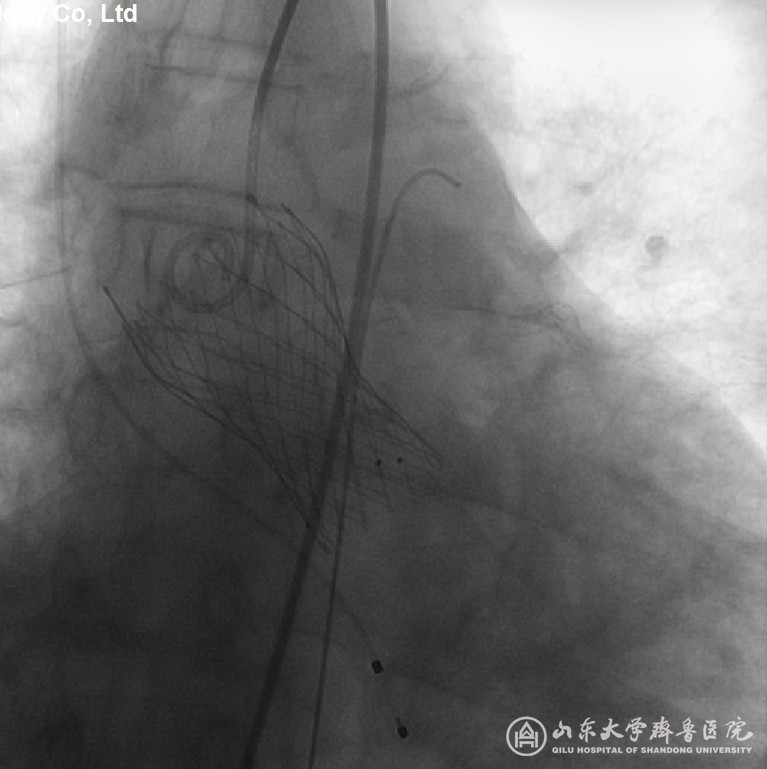

根据不同患者的具体情况,张希全主任多次组织科室及TAVI团队讨论,认为这些患者入院后虽经过积极药物治疗,或血滤等其它治疗,但病情均危重,心功能差。结合STS评分,这些患者行传统开胸体外循环下瓣膜置换手术风险极大,并发症高,死亡率高。经过术前详细评估,可行TAVI手术。遂在医务处的质控管理下,经过充分细致地准备,TAVI团队成员在复合(Hybrid)手术室行TAVI手术(图1),其中患者1、患者2、患者3行经皮股动脉途径,应用国产Venus-A介入心脏瓣膜(见图2、图3、图4),患者4行经心尖途径,应用国产J-Valve介入心脏瓣膜。手术均获成功,手术效果满意。

图4 (患者3)植入介入心脏瓣膜,显示位置形态满意